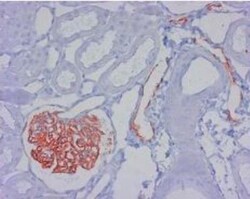

-Immunocytochemistry-Immunofluorescence-NB110-96423-img0006.jpg-250.jpg)